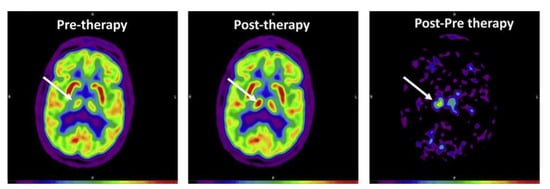

Figure 2.

An example of FDG-PET image, taken from Rudroff et al. 2019 []. FDG-PET transaxial image acquired pre- and post-tDCS therapy. Images are scaled in standardized uptake values normalized to the global mean value (Max = 1.88 for pre-and post-therapy and 0.5 for post-pre therapy). The white arrow indicates the right thalamus, the area with the greatest difference between the images. The color bar describes increasing FDG uptake with increasing signal intensity (from black, indicating no glucose uptake, to red, indicating the greatest glucose uptake).